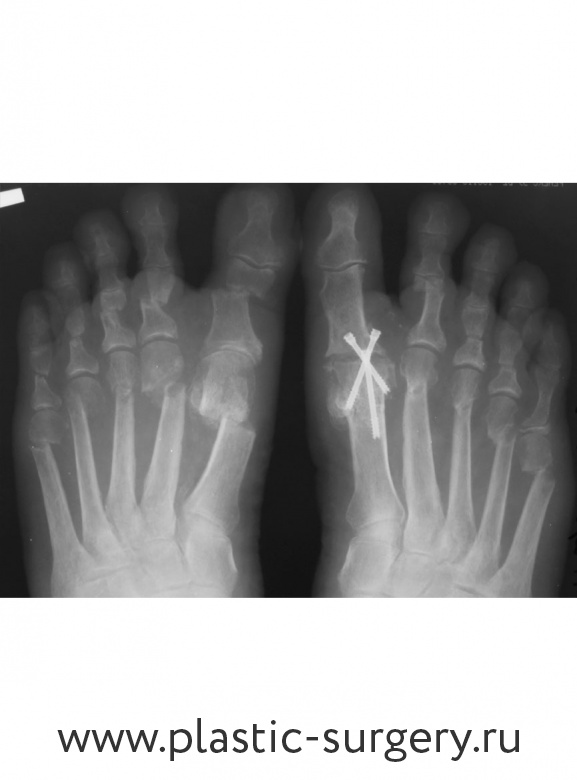

Была проведена операция по коррекции вальгусной деформации стопы.

Вмешательство было очень серьёзным — оперировали сразу обе ноги. От наркоза пациентка отошла быстро и без проблем, в клинике провела всего 3 дня. За это время ей особенно запомнилось отношение персонала — на каждую просьбу сотрудники отзывались с готовностью, помогали даже голову помыть. В клинике курировали весь послеоперационный период, сделали несколько перевязок. Врач осматривал стопы и консультировал.

Уже около 10 лет в клинике применяется чрезпрокольная, малоинвазивная хирургия. В качестве бонуса пациент получает красивую форму стопы. С гипсом и на костылях ходить не надо. С первого дня пациенты Центра передвигаются в специальной послеоперационной обуви. Через 1,5 месяца можно надеть ортопедические сандалии. А через 6 месяцев обычно снимаются все ограничения.

Поперечное плоскостопие III степени, вальгус 1-го пальца стопы, молоткообразная деформация 2-5-го пальца, варусная деформация 5-го пальца. Лечение: малоинвазивная реконструкция переднего отдела обеих стоп. Фото - через 6 мес. после операции.

Поперечное плоскостопие III степени, вальгус 1-го пальца стопы, варусная деформация 5-го пальца, молоткообразная деформация 2-5-го пальца. Лечение: малоинвазивная реконструкция переднего отдела обеих стоп.